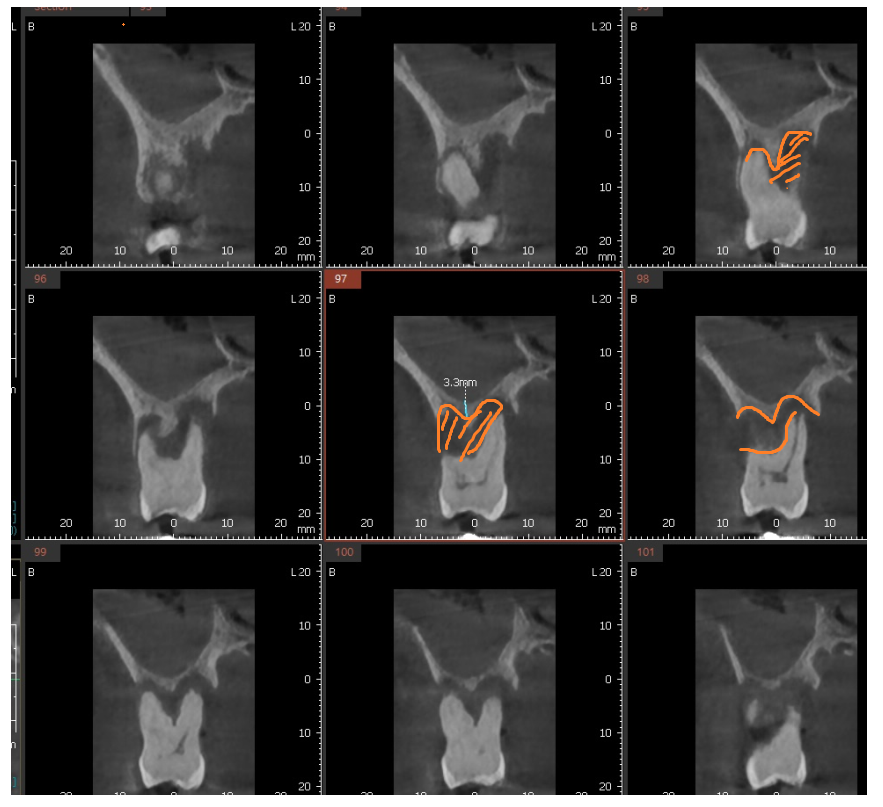

잇몸 뼈가 많이 녹은 x - ray를 보여드릴께요~

240430

빨간색 동그라미 친 부분이

잇몸뼈가 다 녹은 부분입니다.

이 정도가 되면 사실은 이를 뽑아야하는데요.